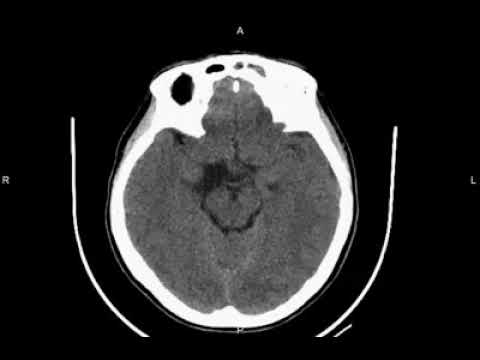

Hellow guys, Welcome to my website, and you are watching Transcallosal-Transchoroidal Fissure Approach for Resection of an Interpeduncular Midbrain Cavernoma. and this vIdeo is uploaded by Barrow Neurological Institute at 2025-05-29T15:25:21-07:00. We are pramote this video only for entertainment and educational perpose only. So, I hop you like our website.